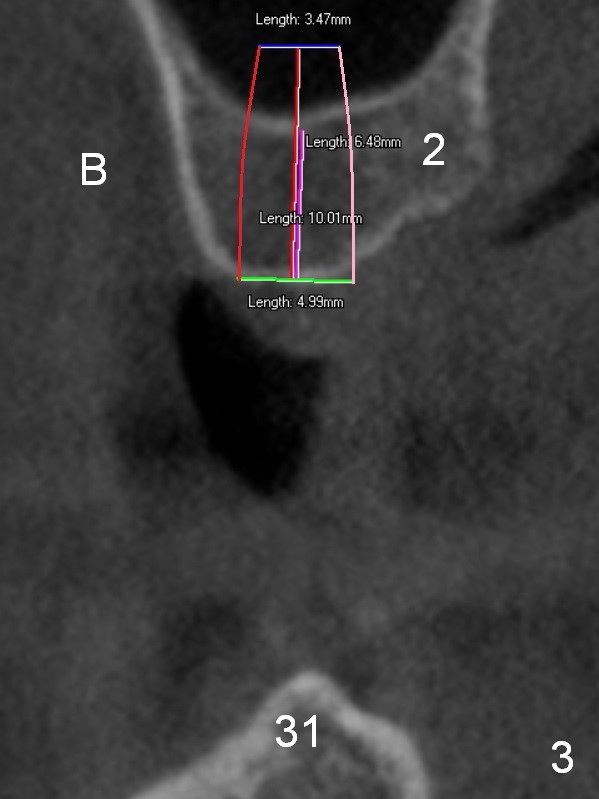

On the other hand, her occlusion is out of order. The teeth #2,14,15,30 and 31 are missing with #3 supraeruption and deep anterior overbite and overjet (Fig.1,2). This may lead to TMD. Alginate impression will be taken for fabrication of night guard or occlusal guard to raise vertical height. If this helps, implants are placed (Fig.3-6), followed by limited or comprehensive ortho to intrude #3, to permanently change her occlusion.